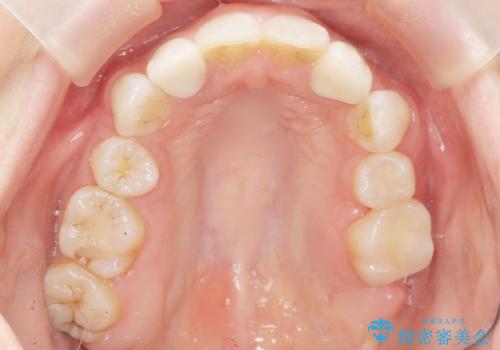

精査したところ、左上の奥歯の間(左上56間)にう蝕を認めました。

う蝕を丁寧に除去したのち、セラミックインレーによる修復を行いました。

セラミックインレーの審美的な仕上がりと自然な咬み心地にご満足頂けました。

「フロスを通したときの嫌な臭いもなくなった」と喜んで下さいました。

インレーの種類:セラミックインレー(e-max press)